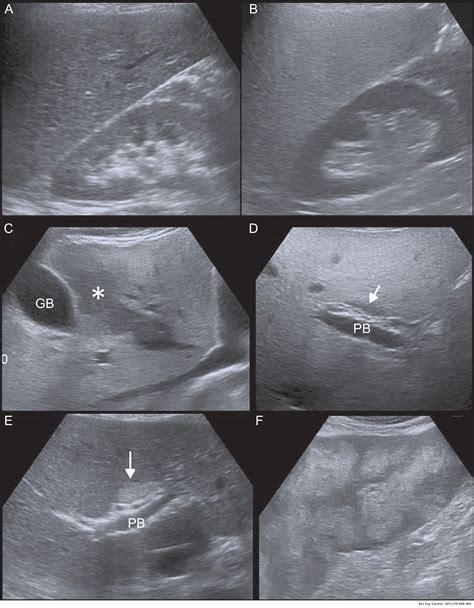

While a normal liver ultrasound is the desired outcome, there are several common findings that may be detected during the procedure. These include:

• Fatty Liver Disease: Excess fat accumulation in the liver, which can be benign or indicative of more serious conditions like non-alcoholic fatty liver disease (NAFLD).

• Cysts: Fluid-filled sacs that can form in the liver. Most cysts are benign and do not require treatment.

• Tumors: Abnormal growths that can be benign or malignant. Further testing is usually required to determine the nature of the tumor.

• Hepatitis: Inflammation of the liver, often caused by viral infections or autoimmune disorders.

• Cirrhosis: Advanced liver disease characterized by scarring and loss of liver function.